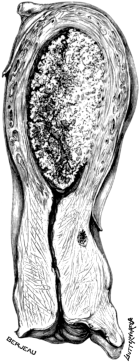

| 4. | A Tuberculous Fallopian Tube and Ovary: Entire and in Section | 24 |

| 5. | Primary Cancer of the Fallopian Tube | 27 |

| 6. | A Section of Primary Cancer of the Fallopian Tube | 27 |

| 7. | A Gravid Fallopian Tube | 30 |

| 8. | A Gravid Fallopian Tube, containing Twins | 32 |